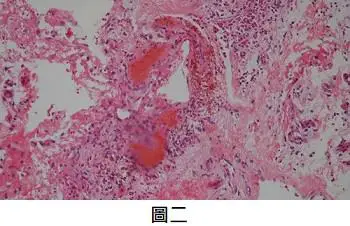

第2張圖(H&E低倍病理):

- 真皮層見多個大小不一之擴張血管樣腔隙,腔內充盈红血球。

- 血管壁由單層扁平內皮細胞構成,無惡性細胞增生、無stromal retraction或腫瘤細胞核異形。

- 病理意義:典型血管擴張(vascular ectasia),非瘤細胞增生,符合venous lake。